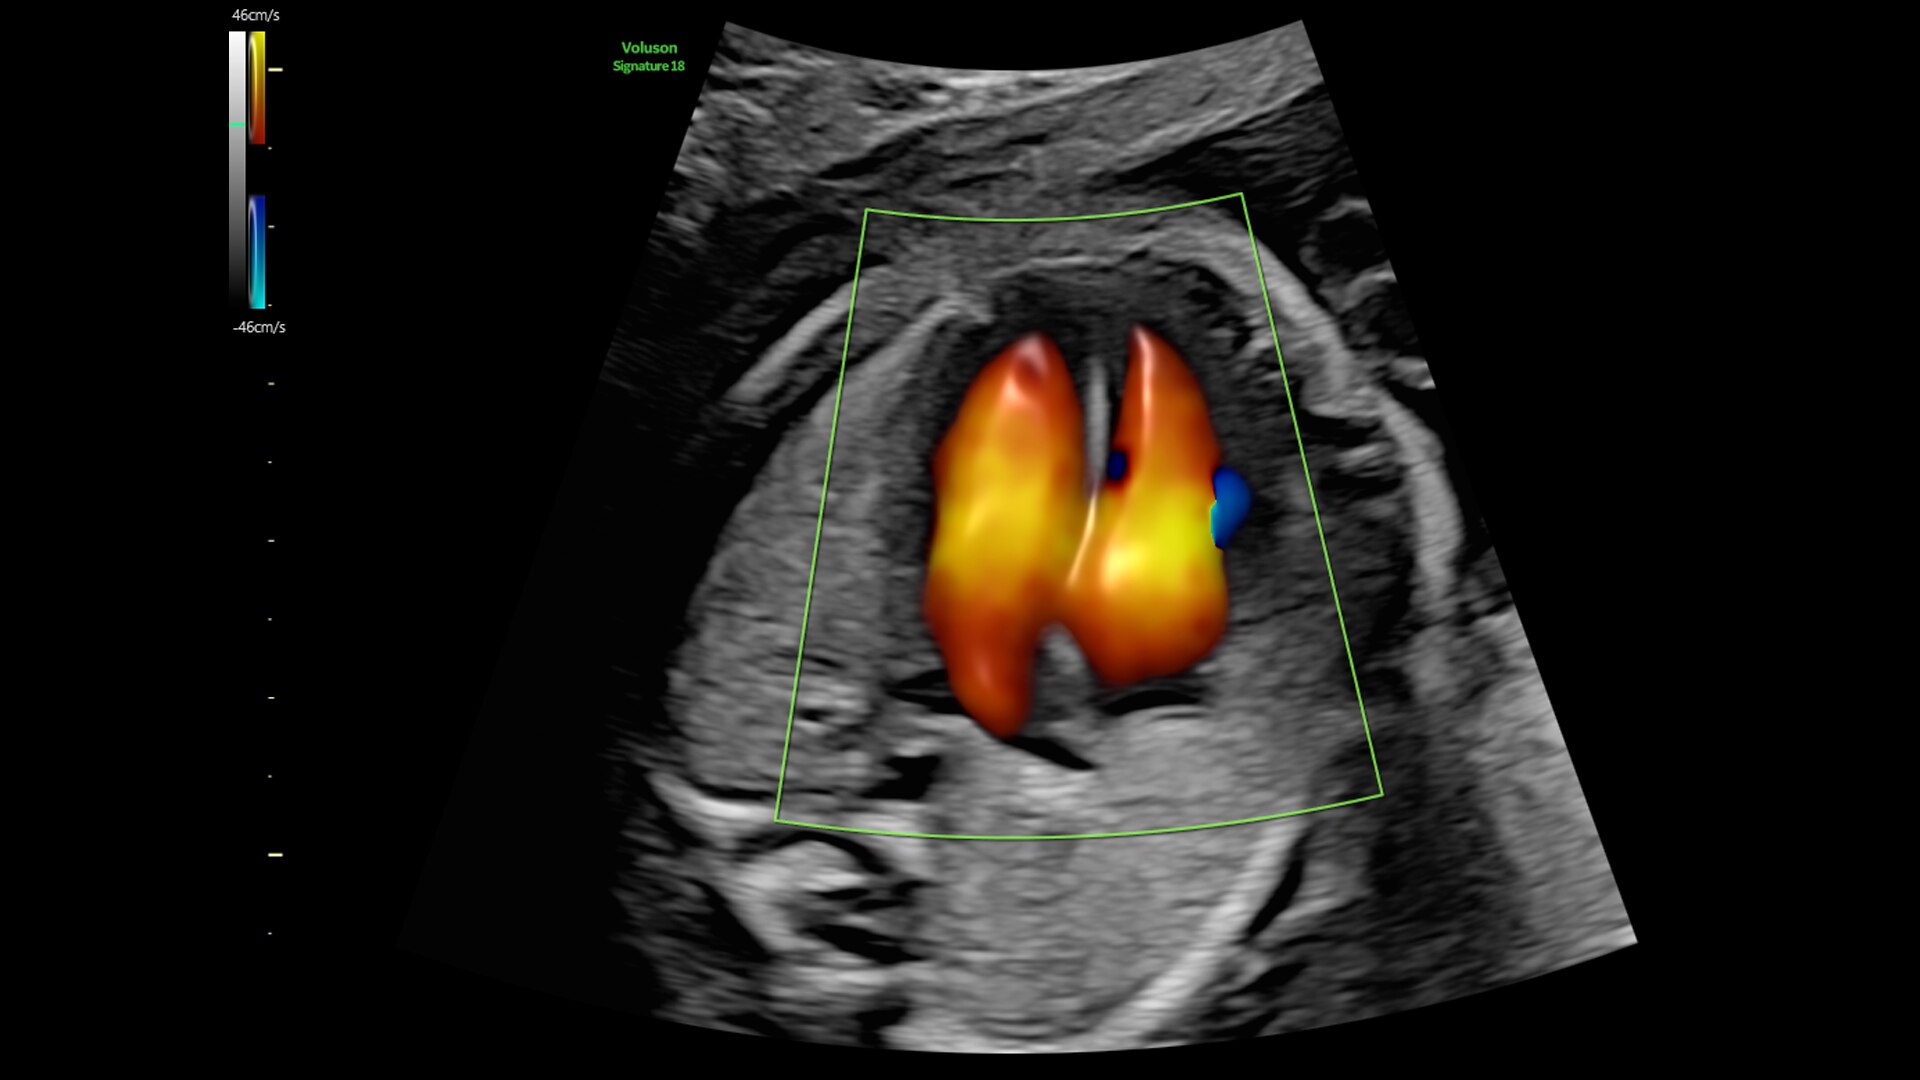

Radiantflow

Fast, easy 3D-like blood flow visualization

Next level color Doppler delivers exceptional sensitivity for easy, fast visualization of blood flow, revealing even the tiniest vessels.